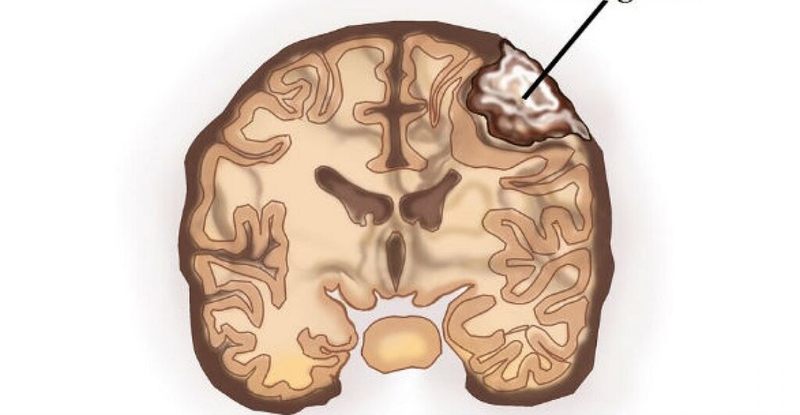

U màng não là một loại khối u nội sọ thường gặp nhất trong các loại khối u nguyên phát ở vùng sọ não. Đây là một bệnh lý lành tính nhưng rất khó phát hiện sớm do không có triệu chứng rõ ràng. Trong khi đó, chụp MRI màng não là phương pháp tuyệt vời nhất trong tầm soát và phát hiện ra bệnh u màng não. Bác sĩ có thể quan sát một cách rõ ràng về hình thái, kích thước và mức độ xâm lấn của khối u.

Màng não bao bọc đại não được cấu tạo bởi 3 lớp màng: Màng nhện, màng mềm và màng cứng.

U màng não thường xuất phát từ tế bào màng nhện và có thể phát hiện ở bất vị trí nào của màng não như nền sọ, vòm xương sọ, tủy sống hoặc rễ thần kinh. Hầu hết các ca bệnh u màng não đều là lành tính, chỉ có một vài trường hợp chuyển sang u ác tính.